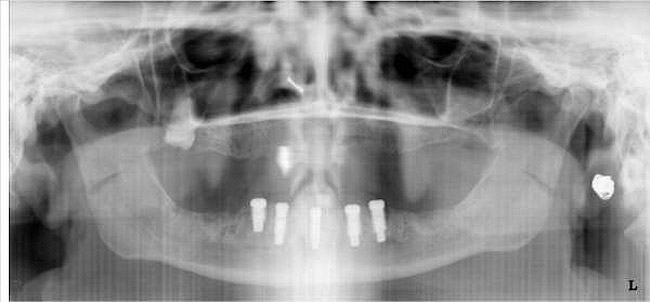

There are several ways to diagnose periodontitis. In addition to soft tissue evaluation, one of the most common and accurate methods is to use a periodontal probe in affected areas and record probing depths. Bleeding on probing is another indication of unhealthy periondontal tissues. Radiographs can be used, but they have limitations in initial diagnosis because bone loss is typically associated with severe and chronic periodontal disease; therefore, radiographs are better used to confirm diagnosis. However, vertical bitewings taken over time can be placed side-by-side to detect even slight differences in contrast.

There are two treatment plans for a patient with advanced periodontal disease—one is set by the general practitioner, and the other is set by the periodontist—and for both of them to work as they should, communication must be open and often. They should look at radiographs together, plan treatment together, and set both short- and long-term goals for the patient.